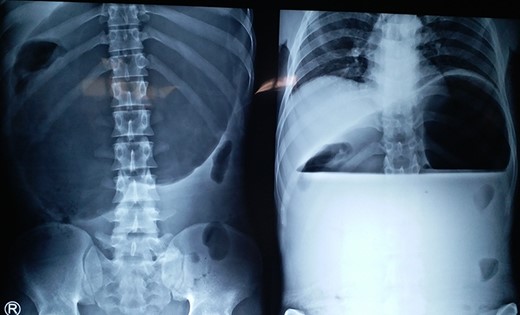

A 25-year-old-male presented to emergency department with 2 days of abdominal pain and non-bilious vomiting. His vitals were stable. The abdominal examination revealed epigastric fullness. There was no tenderness or organomegaly. The laboratory investigation showed normal hemoglobin (12.6 gm/dl), leukocytosis (18 200 cells/mm3) and normal renal function test and serum chemistry. Chest and abdominal X-ray showed elevated left hemi-diaphragm, grossly dilated and spherical stomach with large air-fluid level occupying whole of the upper abdomen (Fig. 4). The diagnosis of gastric volvulus was made and further confirmed by CT. Nasogastric decompression was attempted, but was futile. Patient was resuscitated, injectable broad-spectrum antibiotic commenced and planned emergency laparotomy. At surgery, organo-axial gastric volvulus was seen lying totally in the abdominal cavity, which was de-rotated and series of anterior abdominal wall suture gastropexy performed to prevent recurrently. The patient had an uneventful postoperative course. He was discharged on Day 7. At 28 months follow-up, the patient is asymptomatic.

X-ray showing a markedly distended and spherical stomach suggesting gastric volvulus.